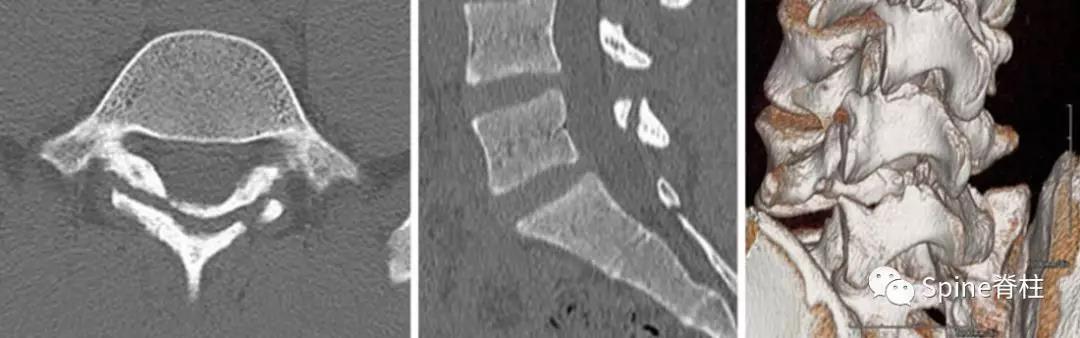

图:L4全椎板裂16岁男孩,3年严重腰痛,后伸受限其中L5椎体骶化